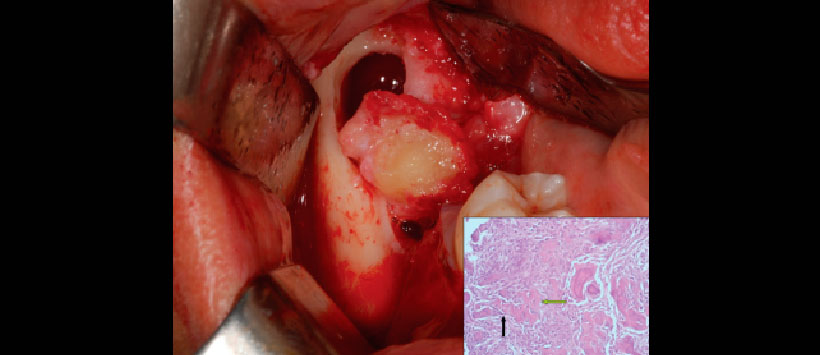

Figura 2: Remoción de la lesión junto a la exodoncia de la pieza 4.7. Confirmación histopatológica de displasia cemento-ósea.